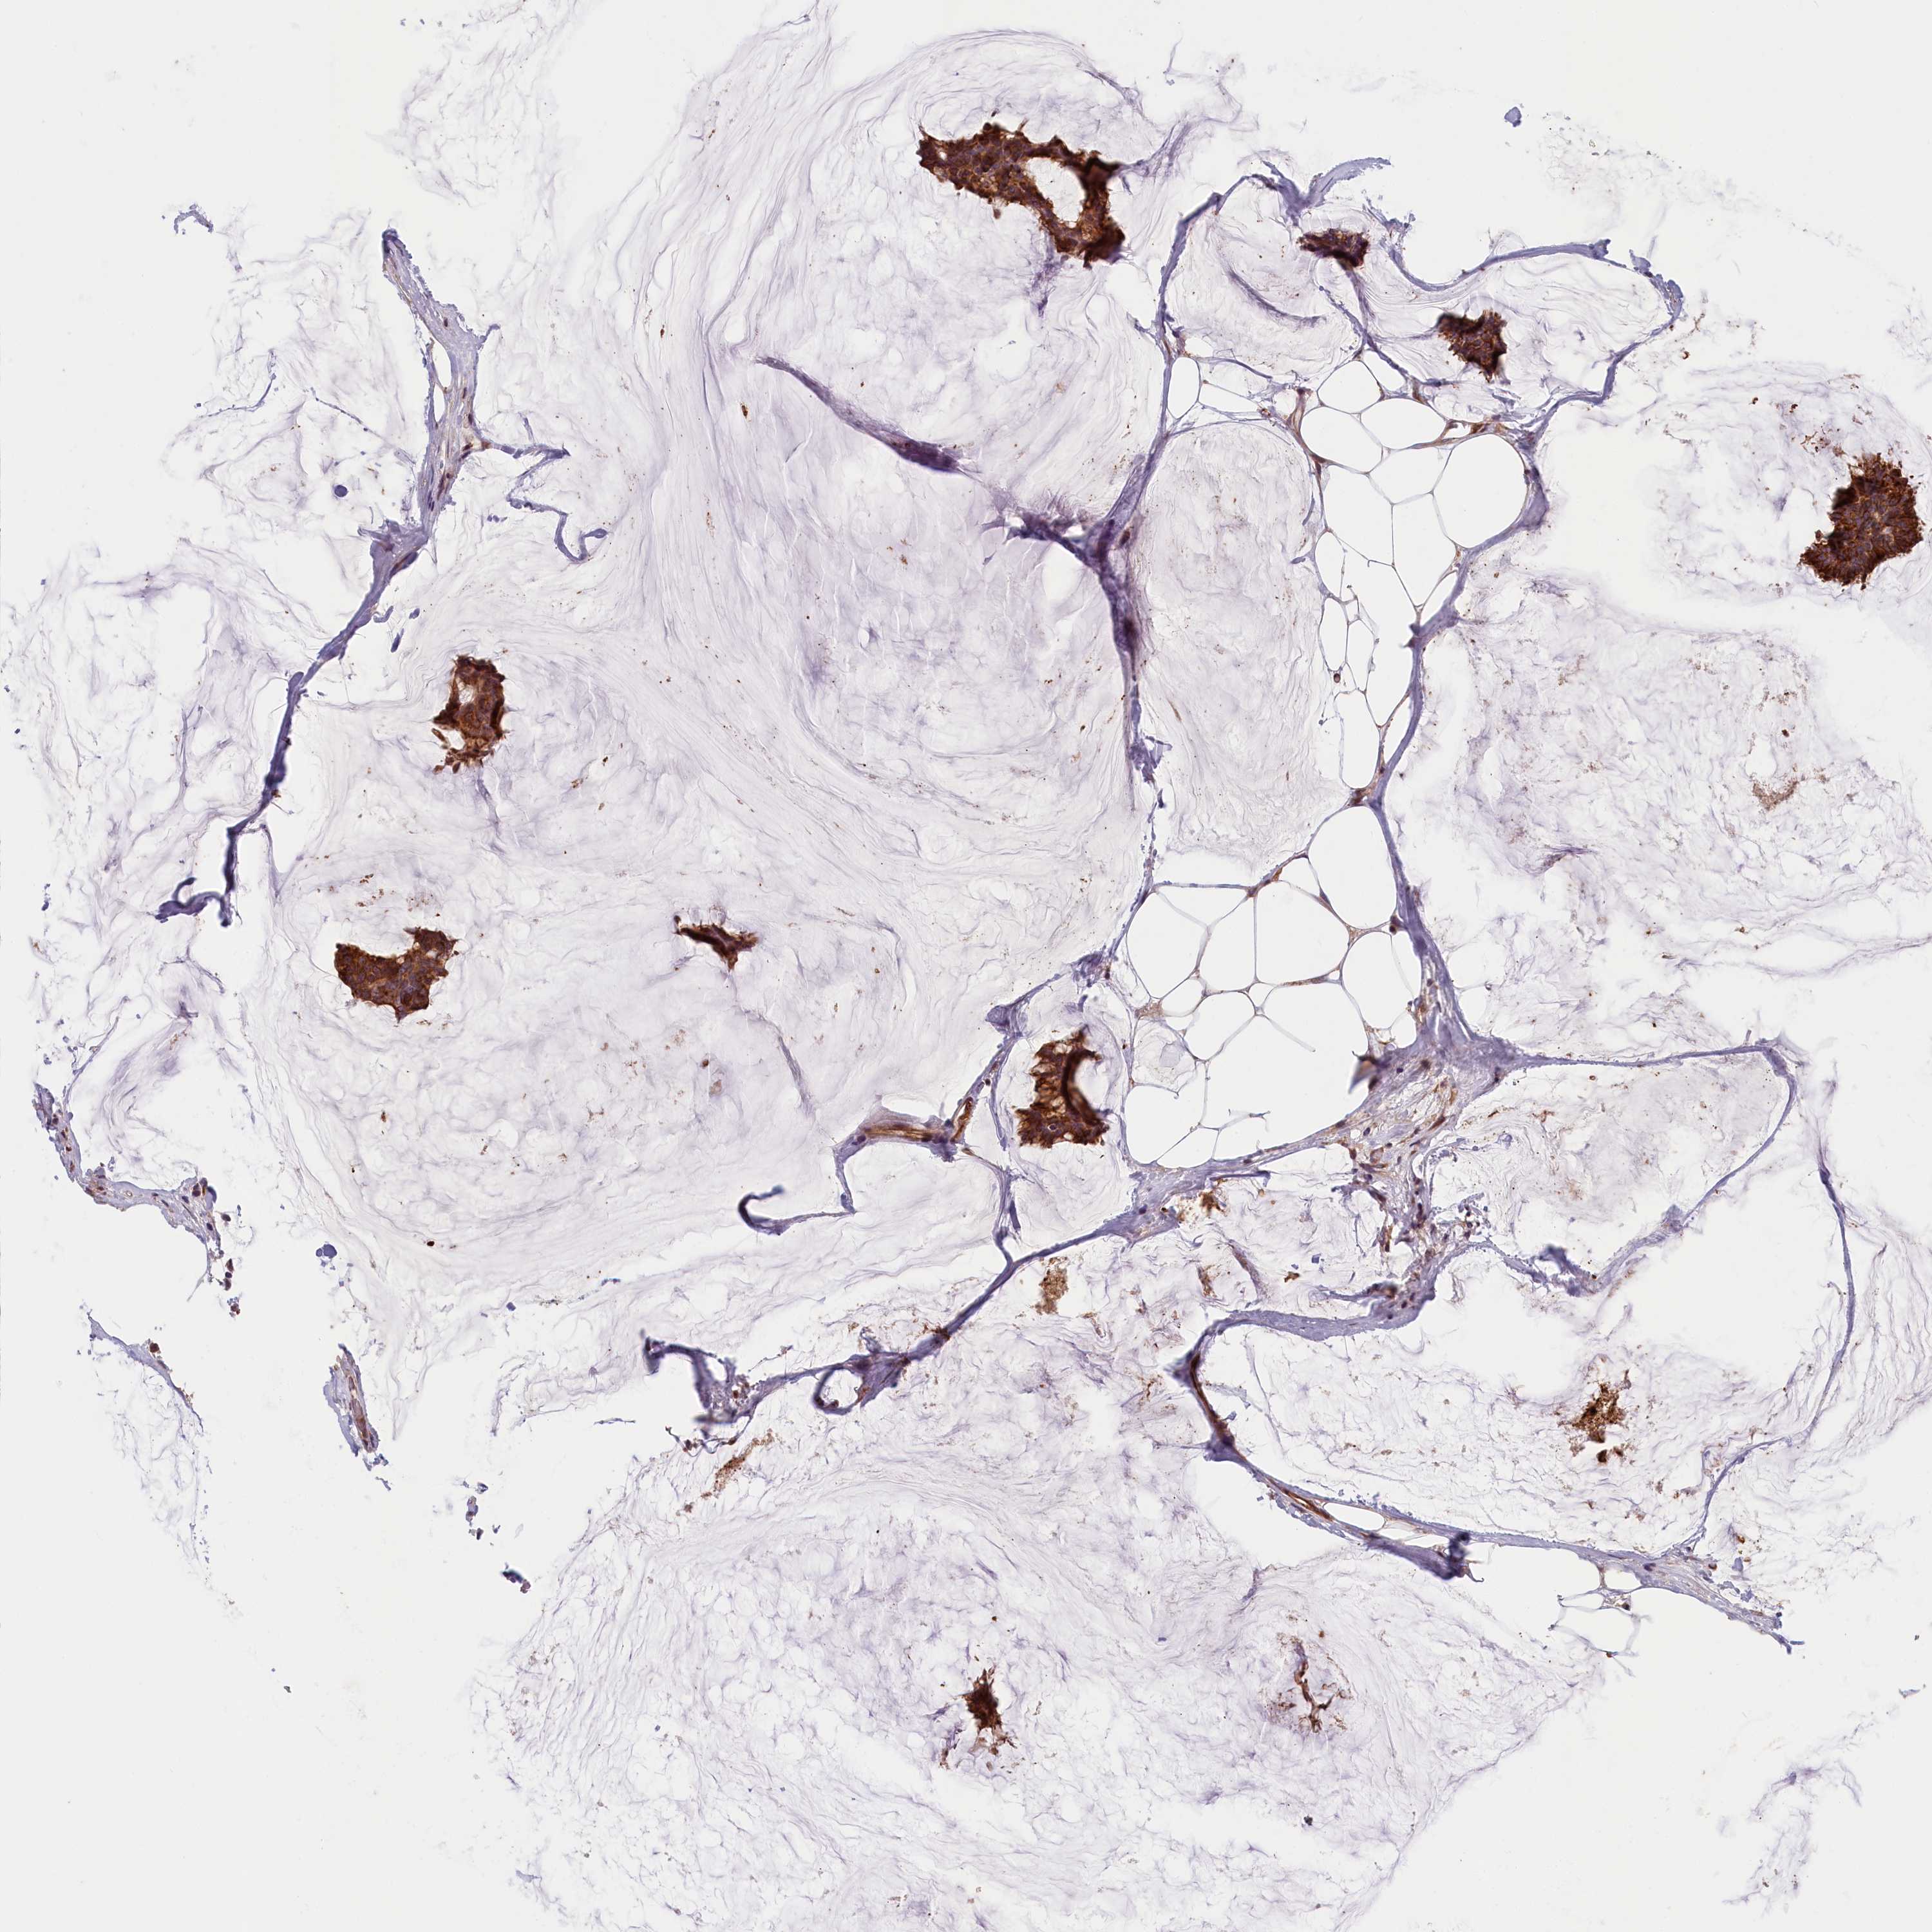

CANCER BREAST CANCER Show tissue menu

Breast cancer

Human cancer